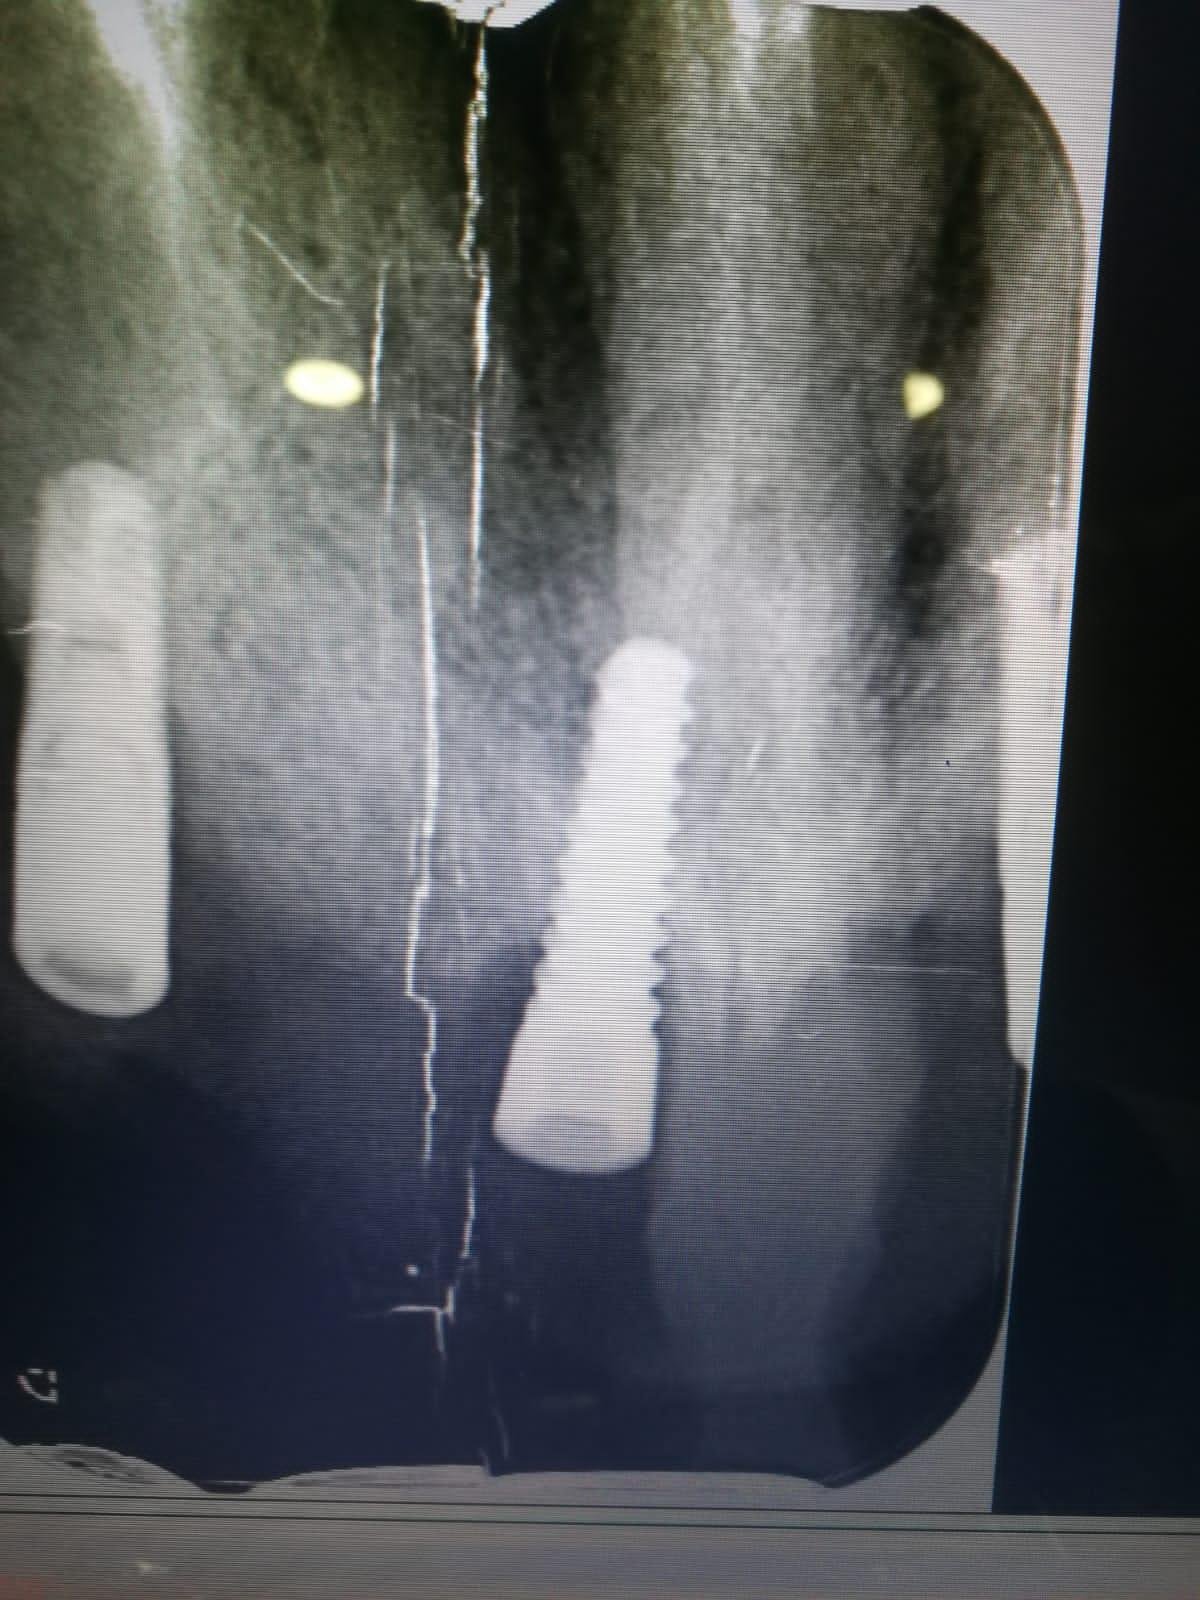

Paciente que le colocaron el implante en Marruecos y necesitaría cargarlo.Muchas gracias compañeros!

El implante que deseas saber es de la marca 3M IMTEC, modelo Endure. La plataforma es de 4,3 mm y el diámetro del implantes de 3.5 mm. Tendríamos que mirar dónde puedes conseguir los aditamentos en España, dado que, no es muy fácil conseguir ese tipo de aditamentos. Esperamos haberte podido ayudar.